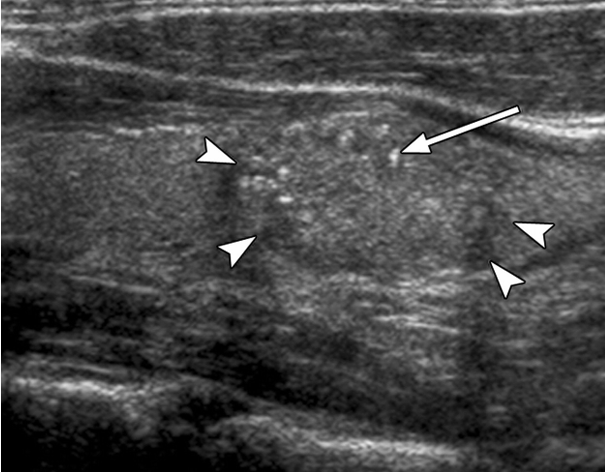

US features of nodules- benign, maligant

-halo sign

-microcalcifications